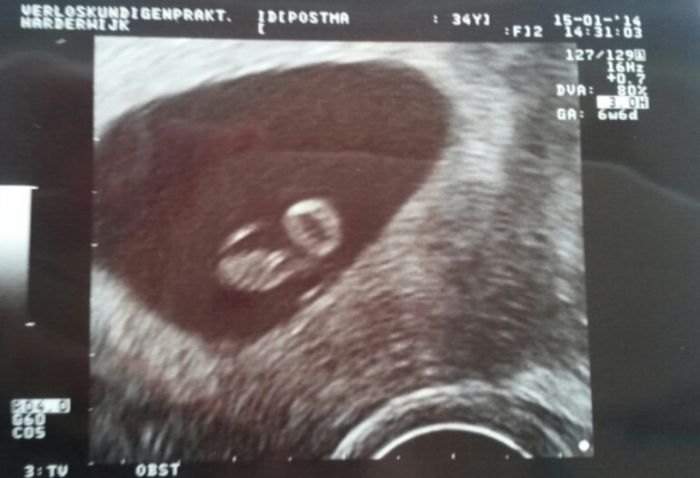

Holky, tak spousta vody v deloze, perfektni misto kde lezi, silne srdicko. Neverila jsem, ze tohle nekdy uvidim. Je uzasny!